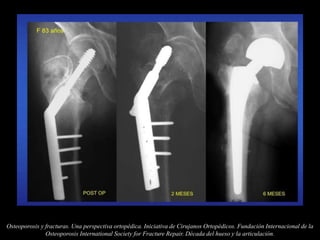

Osteoporosis y fracturas. Una perspectiva ortopédica. Iniciativa de Cirujanos Ortopédicos. Fundación Internacional de la

Osteoporosis International Society for Fracture Repair. Década del hueso y la articulación.

Tratamiento de las fracturas

osteoporóticas

Dr. Cs. Alfredo Ceballos M, Dr. C. Roberto Balmaseda M. Osteoporosis y osteosíntesis. Centro de Investigaciones Médico

Quirúrgicas (CIMEQ). La Habana, Cuba.